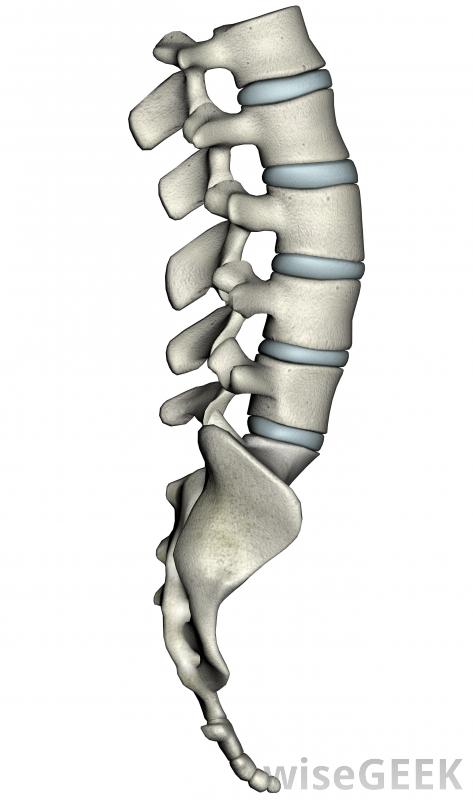

脊髓从大脑向下延伸到腰椎区域。

脊椎,或者叠在一起或者融合在一起。脊椎融合的部分组成了骶骨和尾骨,剩下的24个椎骨则堆积起来。在椎骨内,脊髓从大脑向下延伸到下腰部。此时,脊髓分裂成神经集合,其中一些它们通过脊椎的缝隙进入人体。每个椎骨之间有椎间盘,当脊柱弯曲或扭曲时,这些椎间盘起到缓冲作用。这些椎间盘还保持椎骨之间的间隙开放,以便神经可以安全地通过。